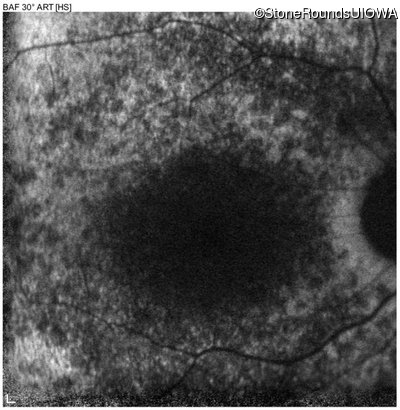

Age at visit: 6 years

OD OS

This 6 year old male first experienced a loss of visual acuity at age 5. His acuity was previously normal. He is otherwise healthy.